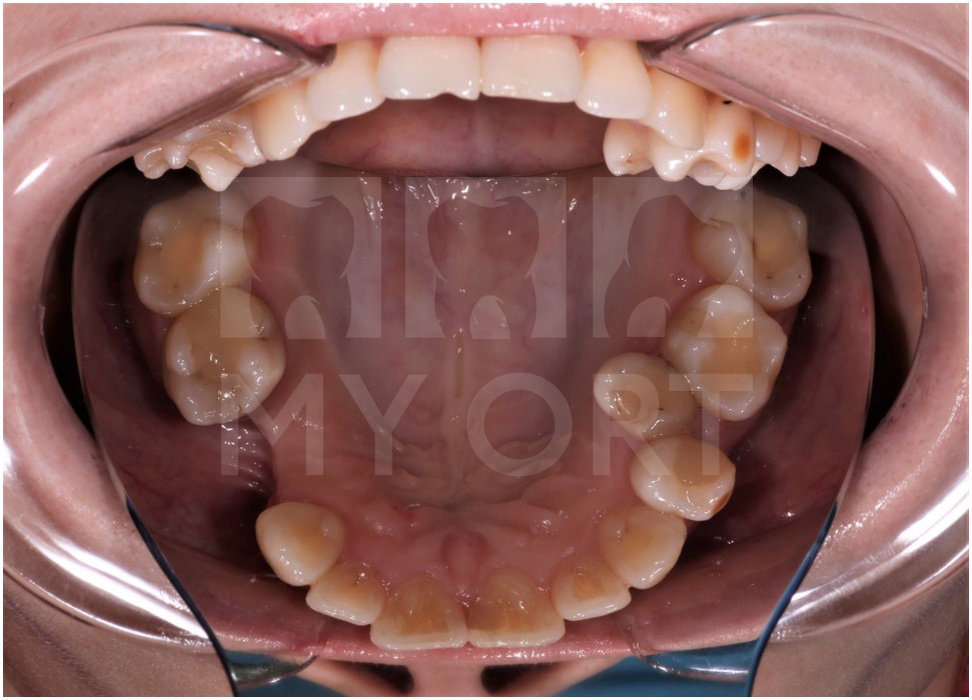

Верхняя челюсть ДО

Нижняя челюсть ДО